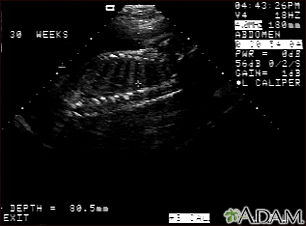

Ultrasound, normal fetus - spine and ribsBackUltrasound, normal fetus - spine and ribsThis is a normal fetal ultrasound performed at 30 weeks gestation. In the middle of the screen, a clear outline of the spine and ribs is visible. The cross hair is between two ribs just above the spine. E-mail FormEmail ResultsName:Email address:Recipients Name:Recipients address:Message: